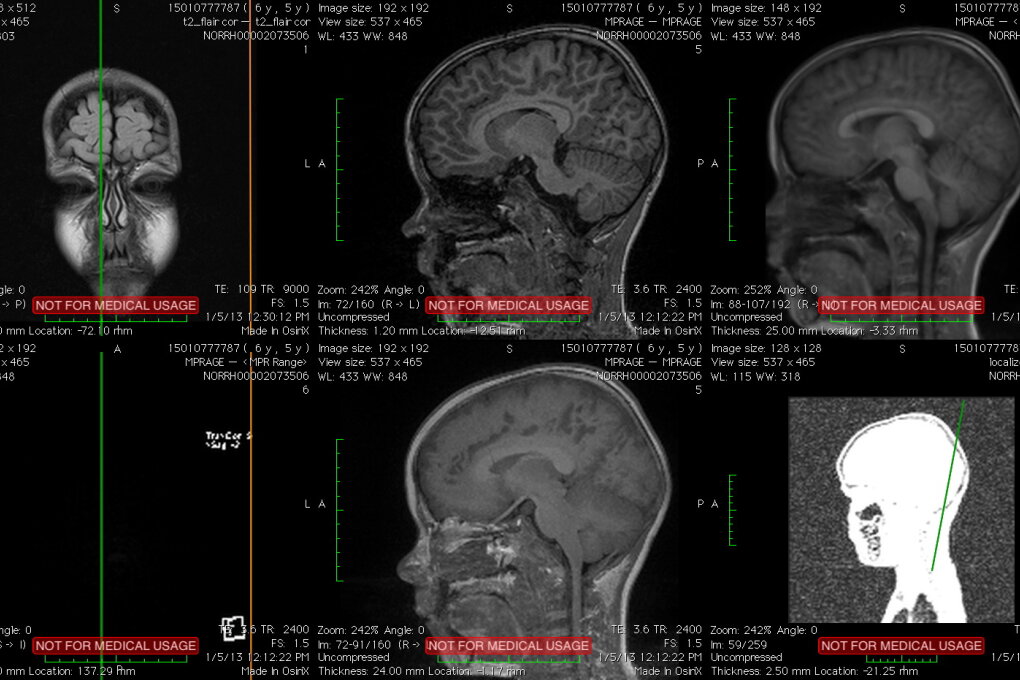

One of the presented artwork is Brain. Brain is a series of video products derived from personal artistic research on modern scientific discoveries and technological developments. Haraldur have MRI images of my son's brain and with the help of scientific software that can focus on the thickness of the pulp, I have come across an endless (seemingly) opportunity for representations on this remarkable body. I have started a dialogue with researchers from the Norwegian University and have received positive feedback on possible collaboration. The project has, over time, been supported by Visual Artists' Remuneration Fund, Gallery of Iceland and Atopia Center for Video Art and Experimental Film.

The fascination with the (almost) infinite possibilities of this detecting/imaging – the perfection in capturing the smallest of fibres, their thickness, length and shape – led Haraldur to dialogue and collaborate with scientists at the Norwegian University to develop the potential of his art practice. The artist has moved the still images through digital technologies into an audiovisual work in which the exact scientific data, on the one hand very concrete and real, appear at the same time as completely abstract, resembling the living structure of the microcosm. The video consists layers of images and detailed structures in which we penetrate deep into the bowels of the body, specifically the head, the place that controls our physical body, but also houses the mind and the whole elusive realm of thought and imagination. While MRI scans can capture the finest nuances and shades of physical matter, fibers and tissue, they cannot reveal anything about our minds. Haraldur's videos lead us here, into a space of imagination and unexpected poetics; they are a kind of authorial interpretation of the contemporary scientific method. They show that the world around us is best understood neither through the exact scientific method nor through subjective individual imagination, but precisely in the combination of these two seemingly contradictory approaches.